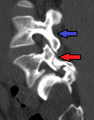

Spondylolisthesis L5/S1. Blue arrow normal pars interarticularis. Red arrow is a break in pars interarticularis